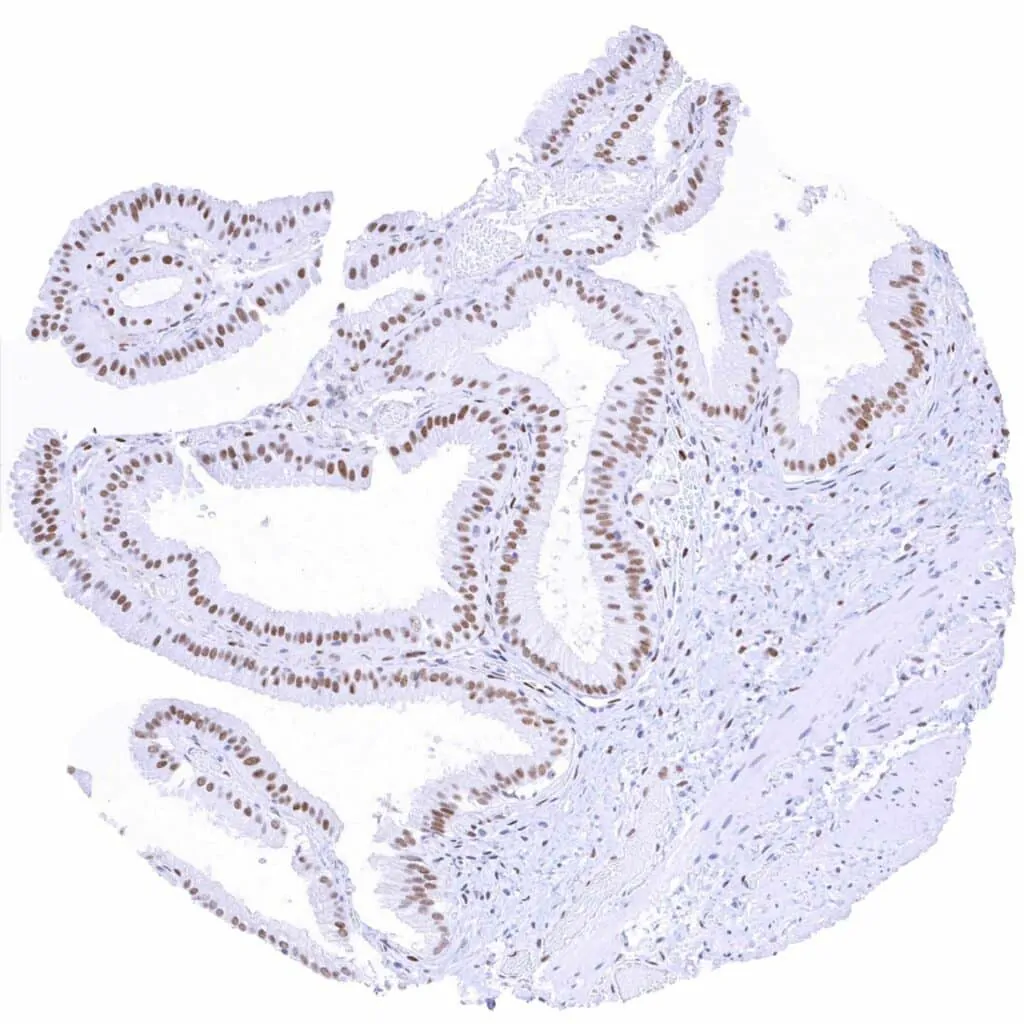

Fallopian tube, mucosa – Moderate TLE1 staining of stromal cells and of a fraction of epithelial cells